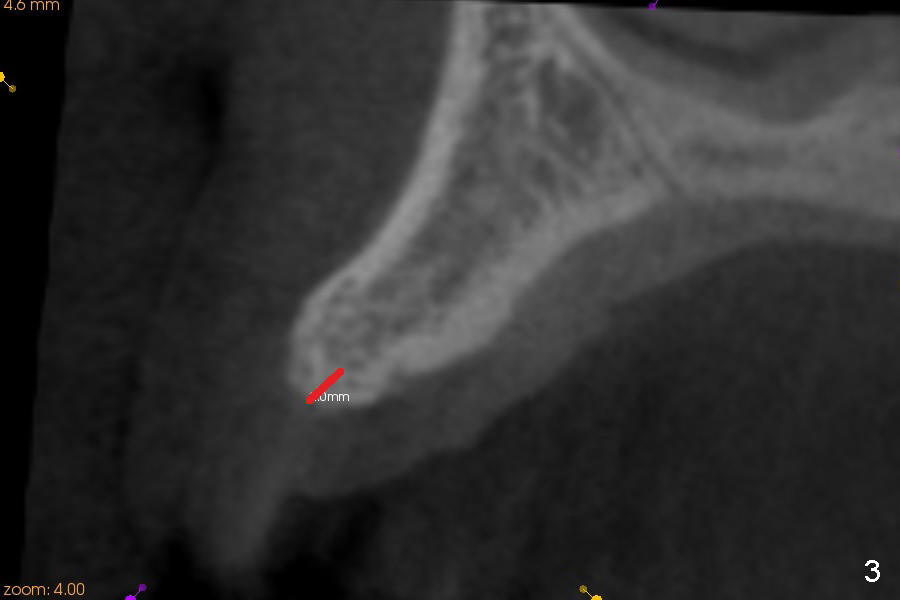

A 45-year-old lady has history of chronic periodontitis. The tooth #6 has lost several years (Fig.1). The buccolingual width decreases (Fig.2 (7mm), as compared to #11 in Fig.6 (10 mm)). Bone expansion is necessary for implantation. It should be done gently, since she is a dental phobic. First the crestal cortex is split with a surgical fissural bur (Fig.3 red line), followed by thin osteotomes (Fig.4 green line: scalpel, bone scalpels (probably until 5 or 6 mm, as indicated by Fig.1 (mesiodistal width)), bone blades (until 5.5 mm)). If the patient cannot tolerate tapping, 1.6 mm pilot drill is used at the depth of 14 mm, followed by bone expanders (probably until 2.9/3.8 using handpiece). As expanders or rounded osteotomes increases in diameter (Fig.5 green arrow), the buccal plate moves buccally (pink arrow). The bone expansion improves cosmetics as well. The implant is planned to be 4.5x14 mm, bone level. Angled abutment is expected. In contrast, immediate implant prevents buccal plate atrophy and avoids bone expansion. How is the surgery?